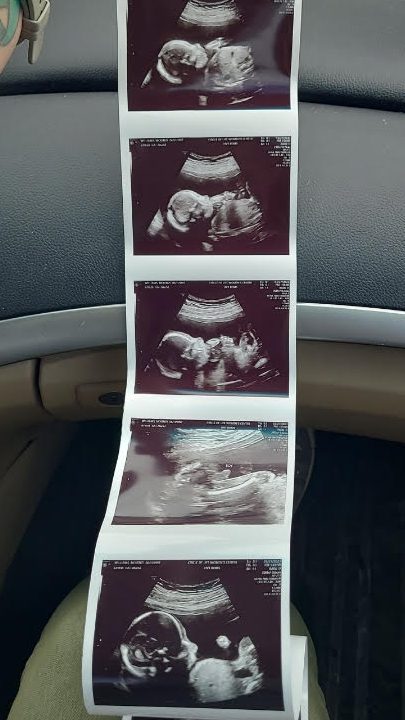

We attended our next appointment when I was 17 weeks with my regular doctor. Before she entered the room, Trent shared how he was finally starting to get over feeling nervous at each appointment, and he was starting to enjoy them, just a little. My doctor did an ultrasound (I get one at every appointment) and was able to confirm that baby was definitely a boy, and everything looked healthy! I then shared with her very casually that I apparently have weird blood, because two blood tests gave me inconclusive results. Thinking her response would be something like “Yup, you just have weird blood, that happens.” I was shocked when she showed some concern. “I don’t want to worry you, but that can be due to problems with the baby or the placenta.” And here we go again with things to worry about..

My body was hot and my mind was racing but also blank as I tried to ingest and understand the many medical possibilities she was listing off. While my initial response was panic and fear, seeing my little bug on that screen, hearing his heartbeat and measurements all being on track, a wave of calm came over me. To conclude our appointment, our doctor apologized and shared that it can also be a lab error and could be nothing! She reminded us that we didn’t want to know genetic testing in the first place, just gender. We now knew the gender, so she left the decision up to us on if we wanted to indulge in further testing or not.

On the way home and the days to follow, I did some research. What an inconclusive blood test can mean, what you can find through genetic testing vs the 20 week anatomy scan, etc. Ultimately, we decided we didn’t want to do further testing. Nothing was going to change the rest of our pregnancy and the love for our baby. We didn’t want the test results in the first place! At our 20 week anatomy scan, the ultrasound tech had zero concerns. Little guy was still measuring and developing great. This was another giant sigh of relief! He was in the 54th percentile and just one day behind my due date.